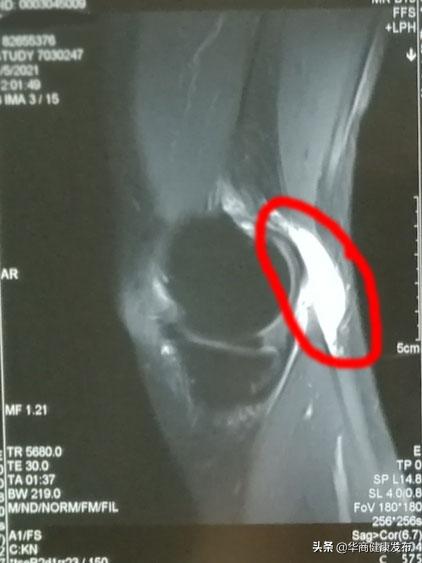

磁共振显示腘窝后方囊肿(红圈部位)

腘窝囊肿常见于35-75岁人群,由于膝关节损伤、感染性因素或退行性变等,使关节腔内压力异常增高,关节液经后关节囊的薄弱区——腓肠肌内侧头与半膜肌肌腱滑囊膨出,这种滑囊存在“单向阀门”的流通机制,关节液进入滑囊内却难以由囊内返流入关节腔,最终形成囊肿不断增大,而几乎不会自然消失。